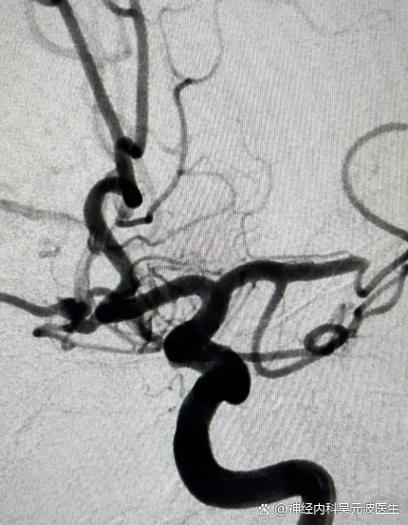

脑梗患者是否需要以及何时进行脑血管造影,这是一个严肃的医疗决策,必须由神经内科或神经外科医生根据患者的具体病情来决定。 脑血管造影是一种有创检查,并非所有脑梗患者都需要。

医生可能会建议做脑血管造影,通常是为了明确以下几个关键问题:

- 寻找病因: 明确导致脑梗死的血管病变原因,如严重的动脉粥样硬化、血管炎、夹层、烟雾病等。

- 评估血管状况: 了解颈动脉、椎动脉颅内段等大血管的狭窄程度、斑块性质、有无闭塞。

- 指导治疗方案: 决定是进行药物治疗、颈动脉支架植入术,还是颈动脉内膜剥脱术。

- 评估侧支循环: 了解大脑在主要血管堵塞后,是否有良好的“备用血管”(侧支循环)来维持供血。